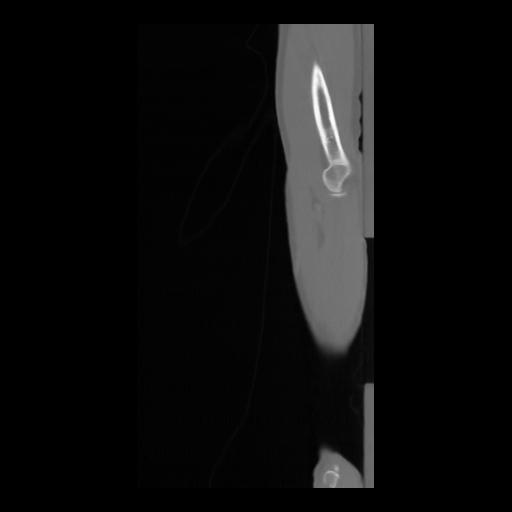

36 CUERPO,CE,Sagittal,3.000,CUERPO,Sagittal,